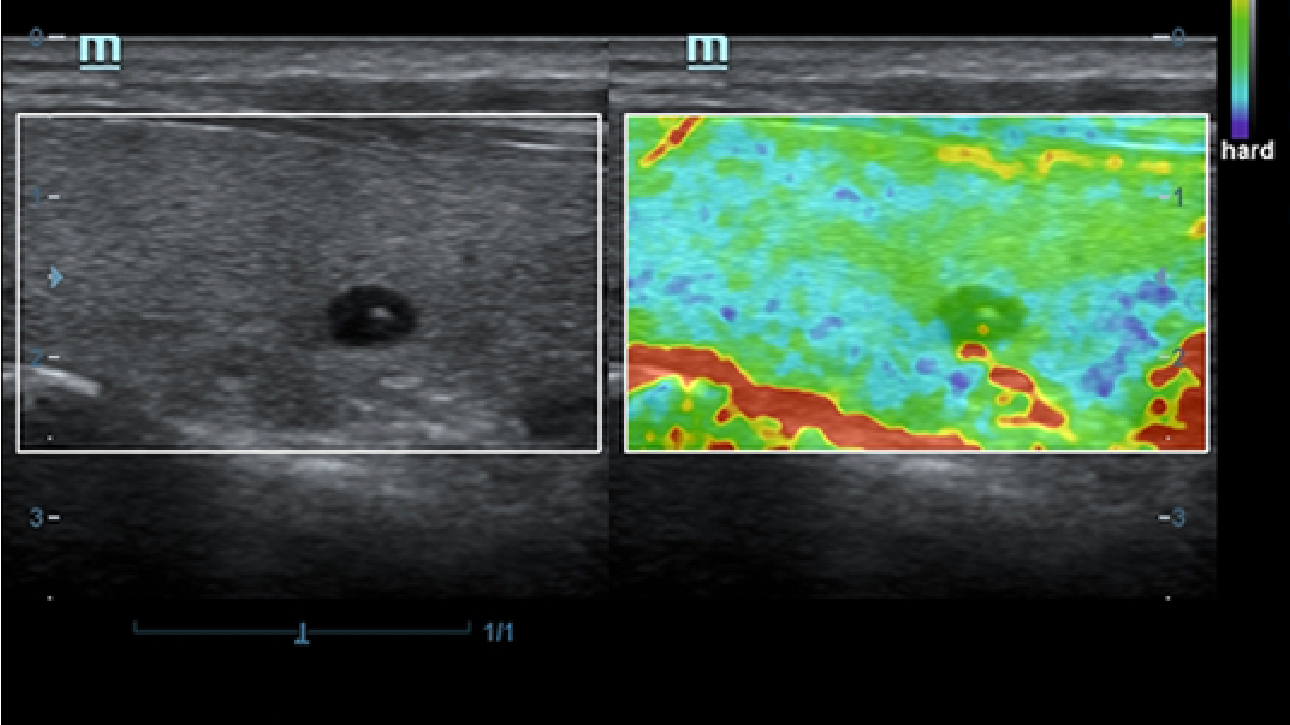

X-Insight, daha geli?mi? g?rĂŒntĂŒler elde etmek i?in kapsaml? bir ??zĂŒmdĂŒr.

Mindrayâin yeni ??zĂŒmĂŒ, geli?en en yeni ultrason teknolojileri ile birlikte, mĂŒ?terilerin g?rĂŒ?lerini klinik gerekliliklerle tam anlam?yla birle?tiren bir ??zĂŒmdĂŒr. Taptaze bir ruhla, gelece?e odaklanarak ve s?n?rs?zl???n pe?inde ko?arak, artan ?l?eklenebilirlikte sĂŒrekli olarak geli?en bir ??zĂŒmdĂŒr.

?ok y?nlĂŒ bir partner olarak, X-Insight'l? DC-60 Exp, her y?nĂŒyle gĂŒnlĂŒk klinik uygulamay? kolayl?kla ve belirsizlik olmadan y?netmenize yard?mc? olacak kapsaml? bir ??zĂŒm sunar.

MĂŒ?teri gereksinimlerine y?nelik g?rĂŒ?ler temelinde, X-Insight'l? DC-60 Exp, eXpress Clarity, eXceptional Intelligence ve eXceeding Experience ile gĂŒ?lendirilerek, hassas g?rĂŒntĂŒlemeyle yĂŒksek verimlilik sa?layacak ?ekilde tasarlanm??t?r.